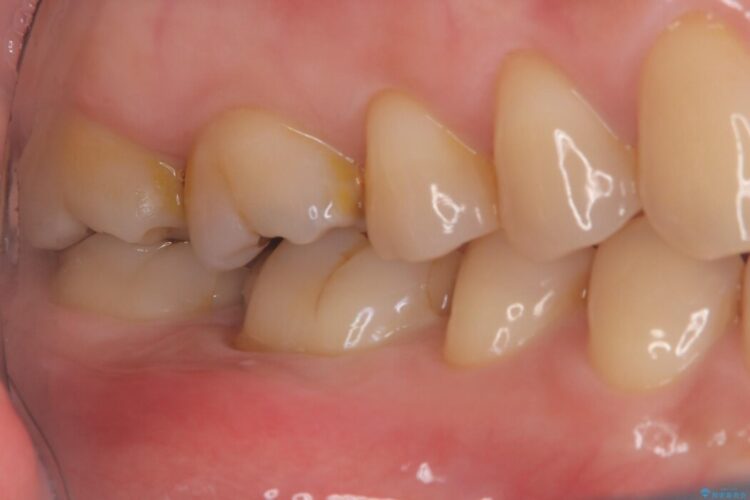

右下奥歯(6番)の激しい痛みと、歯ぐきの腫れを主訴にご来院されました。